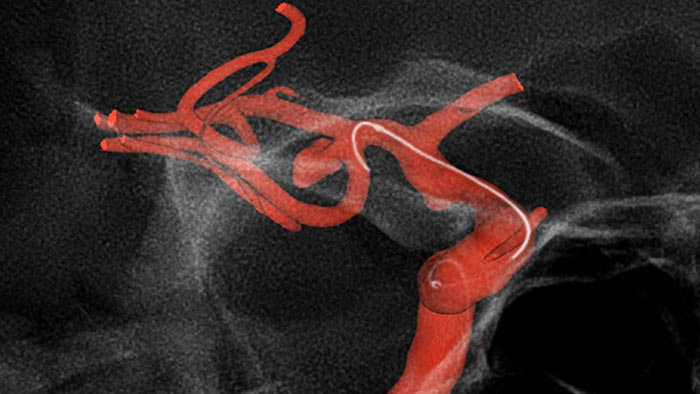

Visualice anatomías patológicas tortuosas en 3D de alta fidelidad

SmartCT Angio

SmartCT Angio proporciona una vista volumétrica en unos segundos para ayudar a evaluar la ubicación, el tamaño, el diámetro y grosor del cuello y la gravedad del aneurisma para la planificación del tratamiento. Los volúmenes 3D se visualizan con alta resolución espacial y compensación automática del movimiento del paciente.